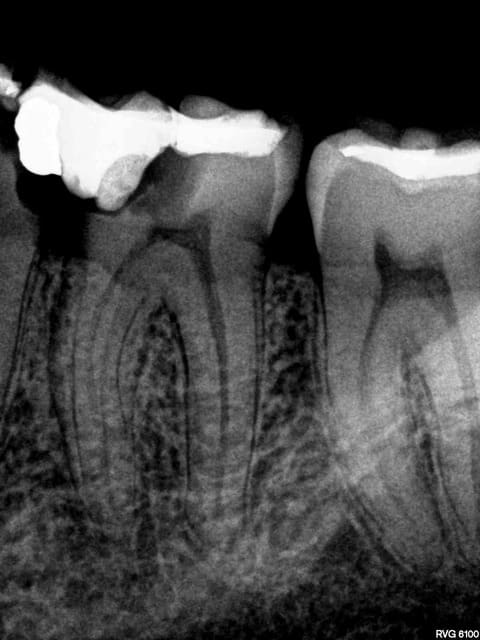

Post de depart !

Honnêtement, la dent est quand même bien niquée !

Fêlure mesiale et distale, le curetage n'est pas complet sur l'arrête restante.

Une couronne, c'est pas une connerie, patient 25-35 on tente l'onlay, patient 45-55, je couronne directement !

C'est une 6 ! 150 kg pression au cm2 !